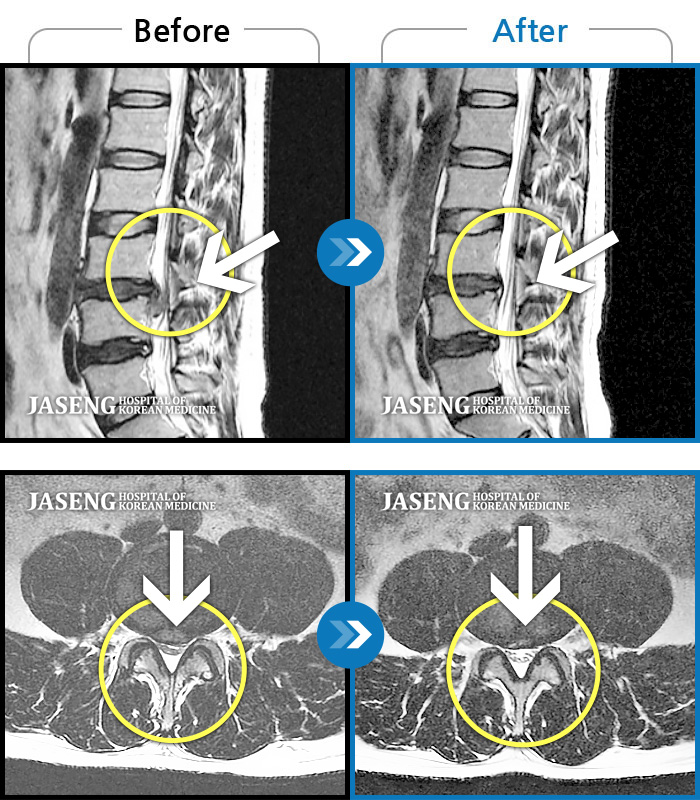

Before

After

환자에게 사전 동의를 받아 동일 조건에서 촬영되었습니다.

개인에 따라 치료 후 부작용이 발생할 수 있으니 의료진과 상담 후 치료를 진행하시기 바랍니다.

좌측 엉덩이 통증 및 허벅지 당김 증상

허리통증, 오른쪽 다리 저림 및 통증